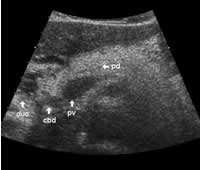

The main bile duct runs from the liver hilum to the right of and above the portal vein into the right dorsal part of the pancreatic head, where it runs vertically into the duodenum. The pancreatic duct typically runs along the body and tail to join the common bile duct near the duodenum. The gastroduodenal artery is sometimes seen in its position along the front margin of the pancreatic head, where it runs in a nearly parallel direction to the common bile duct. Like the common bile duct and pancreatic duct, however, the gastroduodenal artery is not always clearly seen due to its small diameter. The duodenum covers the right and bottom margins of the pancreatic head.

This study shows anatomical landmarks in the bright pancreas of a slightly obese patient:

Transverse planes in caudal direction: